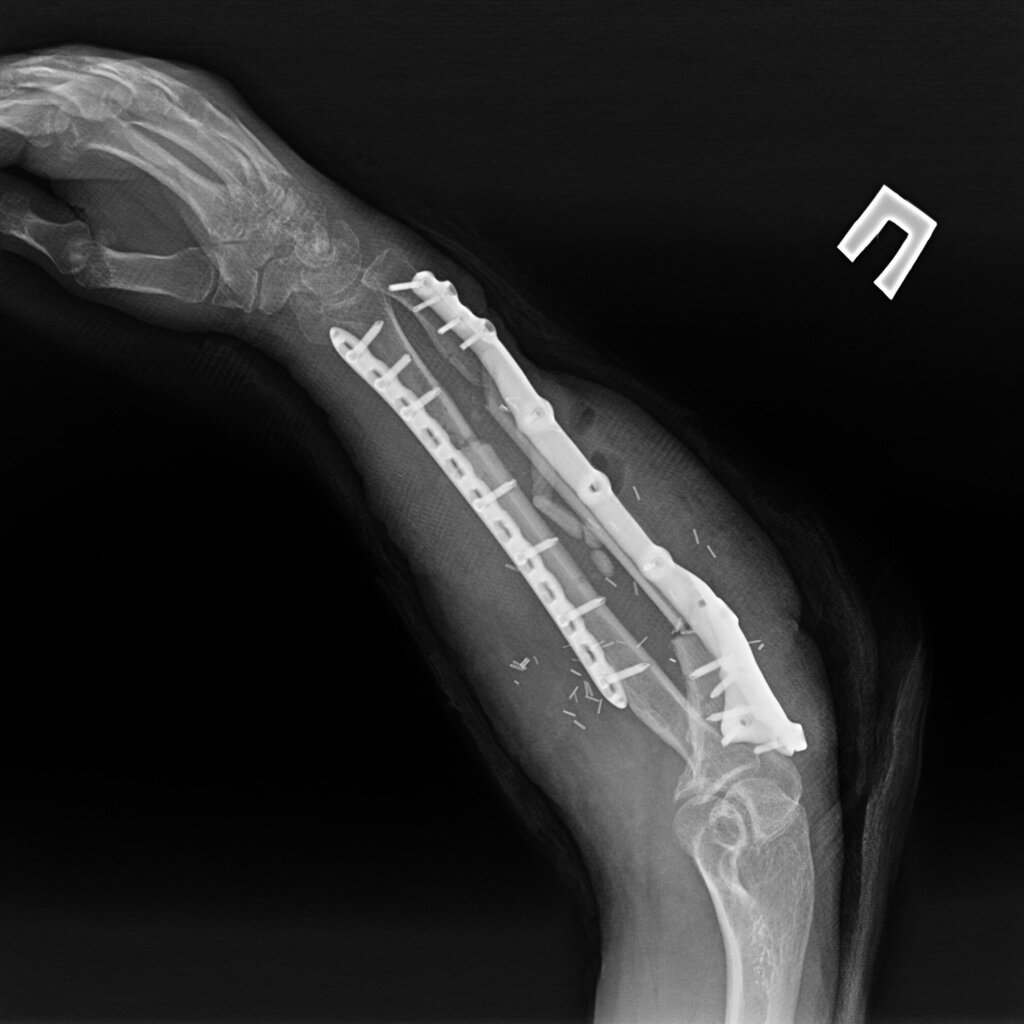

На 95 сутки после ранения проведена реконструктивно-пластическая операция: пластика дефекта мягких тканей и локтевой кости правого предплечья свободным кожно-фасциально-костным малоберцовым лоскутом с фиксацией индивидуальной 3D пластиной, металлоостеосинтез лучевой кости правого предплечья пластиной.

На контрольных рентгенограммах КТ через 4 месяца после реконструктивно-пластической операции отмечается полная перестройка малоберцового трансплантата, замещенного дефекта.